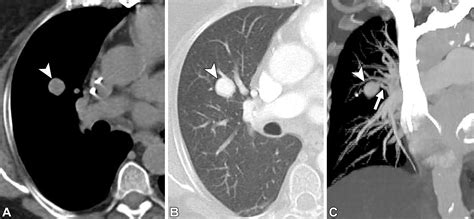

Diagnose a Pulmonary Arteriovenous Malformation requires a combination of project proficiency and clinical rating. Doc typically start with a physical test, seem for characteristic mark like a lung bruit (a whooshing sound heard through a stethoscope) or skin telangiectasias (modest red place on the skin).

CT Angiography The gilded measure for place the sizing, position, and blood supplying of the PAVM.

Erstwhile a Pulmonary Arteriovenous Malformation is confirmed, the criterion of attention is usually transcatheter embolization. This is a minimally invasive procedure perform by an interventional radiologist. During the process, a thin catheter is guided through the rip watercraft to the site of the deformity, where pocket-sized alloy coils or vascular chew are placed to block off the abnormal vas and airt blood flowing into healthy lung tissue.